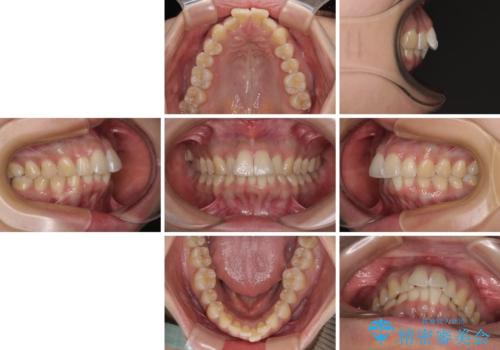

前に飛び出して目立っている前歯を整える インビザライン矯正治療

- 前方に主張した前歯2本を気にして来院された患者様です。

下顎前歯がデコボコしており、その影響で上顎前歯が前方に押し出されている状態でした。

口元が閉じにくいという印象はなかったため、非抜歯矯正にて歯列を整えていくこととしました。

上下左右の親知らずを抜歯し、上下ともに歯列を後方と側方に拡大し、口元を突出させることなくデコボコを解消することとしました。

前歯の形が台形であり、歯列が整ったところでブラックトライアングルが目立つ仕上がりとなったため、IPR(歯と歯の間を削る処置)によって歯の形態を修正し、隙間の目立たない歯列に仕上げることができました。